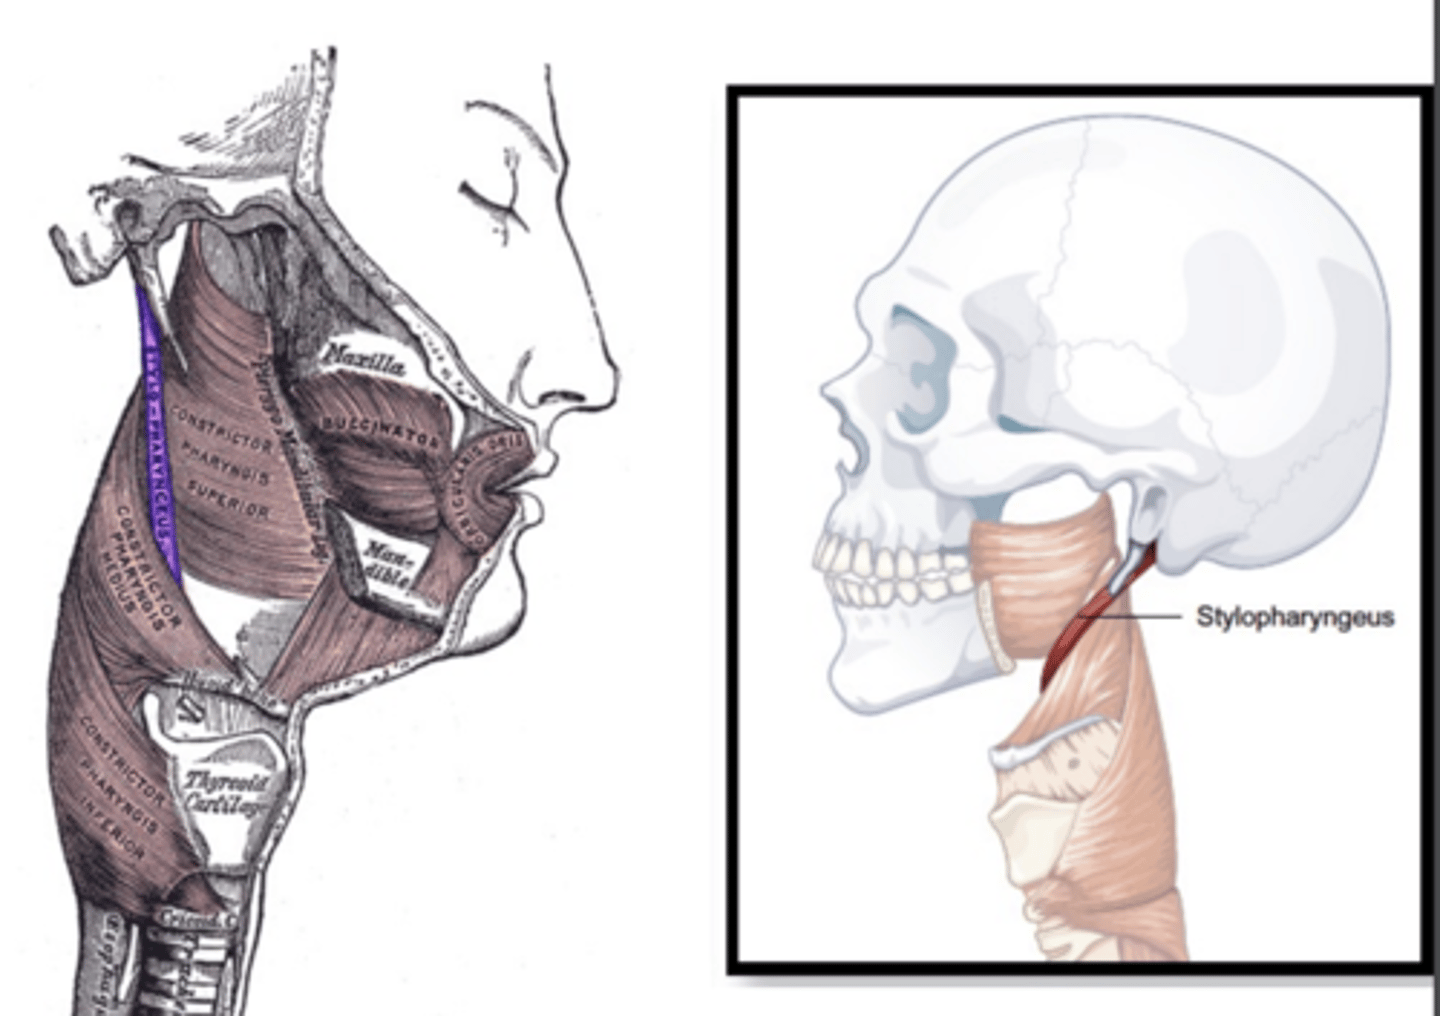

Stylopharyngeus Description

Long thin muscle

Origin - styloid process of temporal bone

Course - inferior, entering between

superior and middle constrictor

Insertion - blend with constrictors, with

some fibers inserting on thyroid cartilage

Action - elevate and dilate pharynx

Stylopharyngeus Figure